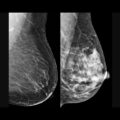

Além disso, a realização de exames de rastreamento e o acesso ao diagnóstico precoce são fundamentais para aumentar as chances de cura. “O câncer não é mais uma sentença de morte. Quando diagnosticado precocemente e tratado de forma adequada, as chances de sucesso são muito maiores”, reforça.